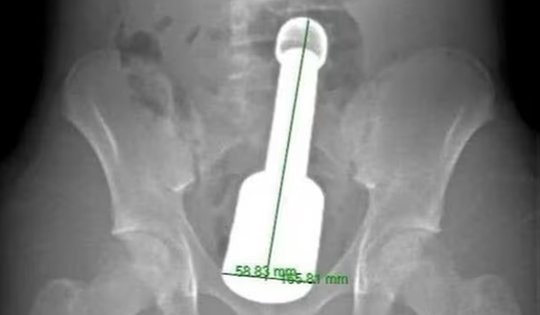

Nam thanh niên 15 tuổi nhập viện vì đau bụng dữ dội, bác sĩ sốc khi phát hiện thứ “đáng sợ” bên trong

Một thiếu niên 15 tuổi phải nhập viện cấp cứu trong tình trạng đau dữ dội sau hành động bồng bột do tò mò. Thăm khám cho thấy có dị vật mắc kẹt trong cơ thể.